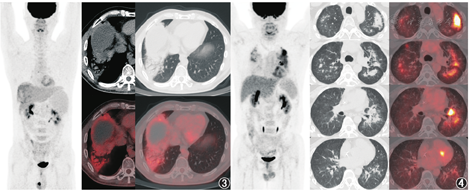

ICIs治疗引发的irAEs几乎可影响所有器官,大部分为轻度至中度,停药后可自行缓解。irAEs的发生率很高,60%~70%的ICIs治疗后患者会出现至少一项不良反应[9],其中皮肤、肠道、内分泌系统(甲状腺、垂体)、肺和肌肉骨骼不良反应相对常见,有时也可发生心血管、血液系统、肾脏、神经和眼部的不良反应,其中神经系统和心脏不良反应的致死率较高,尤其值得关注。由于irAEs与免疫诱发的炎性反应相关,所以irAEs在18F-FDG PET/CT上也可有所表现,在判读PET/CT时需加以留意。除了前面提到的结节病样反应外,18F-FDG PET/CT上可发现的irAEs还包括免疫相关肺炎、结肠小肠炎、甲状腺炎、关节炎、肌炎/筋膜炎、垂体炎、心肌炎、肝炎、胰腺炎等。如图3为1例肝癌患者抗PD-1治疗后新出现右肺下叶实变影,伴支气管充气征,18F-FDG代谢轻度增高,SUVmax为3.3;患者无发热或呼吸系统的主诉或体征,未加用针对性治疗、未停用PD-1治疗,胸部CT随访观察实变范围缩小,临床考虑免疫相关肺炎可能。

影像学上免疫相关肺炎主要表现为不同类型的间质性肺疾病,大致可分为机化性肺炎、非特异性间质性肺炎、过敏性肺炎、弥漫性肺泡损伤几大类[10]。但免疫相关肺炎需要与肺部感染鉴别,二者在肿瘤患者治疗期间都比较容易出现,影像表现有相似,而治疗方向却相反(糖皮质激素与抗生素等)。如图4是1例纵隔大B细胞淋巴瘤患者,曾接受化疗、自体干细胞移植、嵌合抗原受体T细胞回输、抗PD-1治疗,患者抗PD-1治疗8个月后出现了胸闷、气短、血氧饱和度下降,18F-FDG PET/CT示双肺多发磨玻璃、斑片及实变影,以中上肺、中央带分布为著,实变者内见支气管充气影,病灶代谢不同程度增高,SUVmax为9.7,最终临床诊断肺孢子菌肺炎,混合巨细胞病毒感染,予复方磺胺甲恶唑、更昔洛韦、泼尼松治疗后,患者症状缓解、肺部阴影消失。